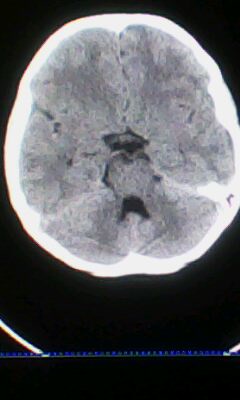

标题: PED3324:男 10岁 右侧 眼不自主抽动 自感颈部不适 [打印本页]

标题: PED3324:男 10岁 右侧 眼不自主抽动 自感颈部不适

蛛网膜下腔出血。

蛛网膜下腔出血可能。

颅脑ct轴位平扫颅内未见明确异常;建议必要时行mri检查。

窗调的不好,图像感觉怪怪的,不好说有什么明显异常,可建议mri检查。

颅脑ct轴位平扫颅内未见明确异常。